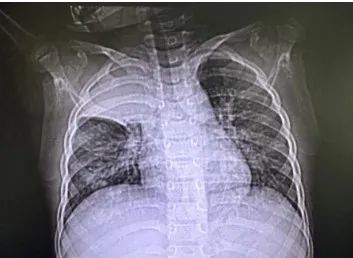

该患儿入院前三天突发咳喘,出现发热后前往上海市儿童医院呼吸科就诊。呼吸专科门诊医生胸片检查发现两肺纹理增多,右上肺高密度影,可能存在感染性病变;随即被收治入呼吸科病房。入院后患儿血氧饱和度最低仅89%,出现呼吸衰竭,紧急肺部 CT 检查发现右肺上叶影像完全消失,右肺少量胸腔积液。